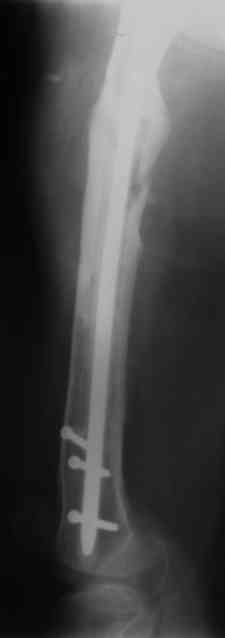

Вчера наш пациент был на контрольном осмотре. Вроде все идет нормально. Рентгенограммы от 25 сентября 2007 г. (прошло 5 месяцев после операции) прилагаю.

В качестве демонстрации лечения канального остеомиелита бедренной кости представляем пациентку (см. parts 2 и 3), которая как раз сегодня была у нас на контрольном осмотре. В мае этого года мы произвели ей фиксацию бедренной кости штифтом-спейсером по поводу ложного сустава и канального остеомиелита бедренной кости. Через 4 недели после операции свищи закрылись. Сейчас она ходит с полной нагрузкой на конечность.

4, 5, 6 - рентгенограммы бедра и фотографии пациентки (прошу прощения за низкое качество рентгеновских снимков) от 7 сентября 2007 г.